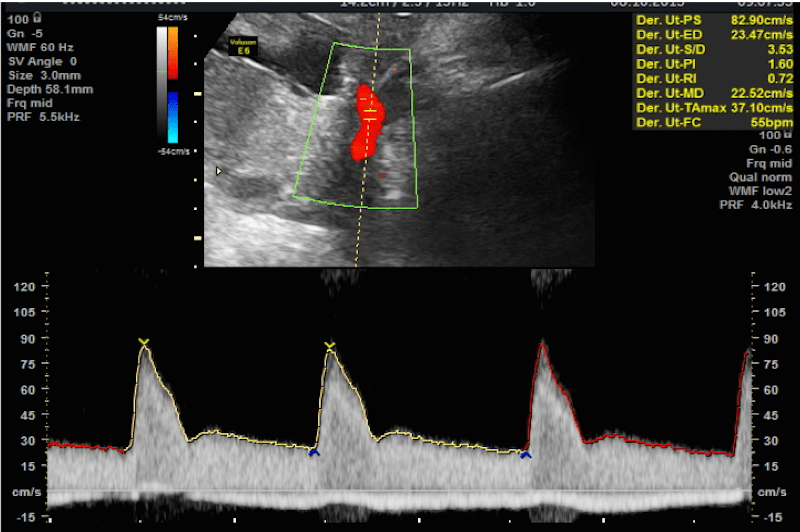

Ecografía Doppler

La Ecografía Doppler estudia el flujo de sangre que pasa a través de las arterias y venas que ponen en contacto la madre, la placenta y el feto.

El estudio de la Ecografía Doppler permite conocer la cantidad de flujo sanguíneo de la circulación, su velocidad y su resistencia en un momento concreto.

Este estudio es una variedad de los ultrasonidos tradicionales, que se utiliza para comprobar el funcionamiento de la placenta y el estado del bebé en gestaciones de riesgo como la hipertensión de embarazo, y los fetos que no crecen bien dentro del útero. En los embarazos múltiples o gemelares, la ecografía Doppler también tiene su utilidad.